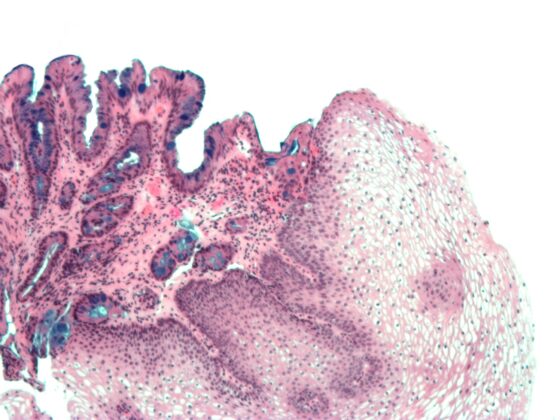

• Risikostratifizierung bei Barrett-Ösophagus

Pathologietest schlägt menschliche Experten

• Rx

• Allgemeine und Innere Medizin

• Gastroenterologie und Hepatologie

• Kongressberichte

• Onkologie

• Studien